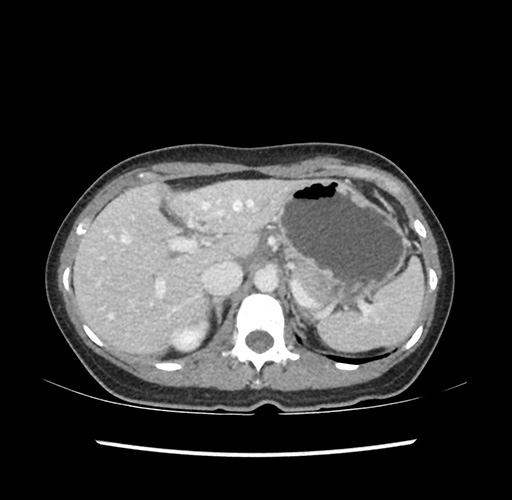

Imaging Analysis

Look through the patient's CT scan to identify any areas of concern for the necessary procedure.

Based on your CT findings, which issue(s) would give reason for "planned slowing down moment(s)" in this case?

Considering a standard left lateral sectionectomy procedure, what step(s) of the operation would you do differently in this case ?